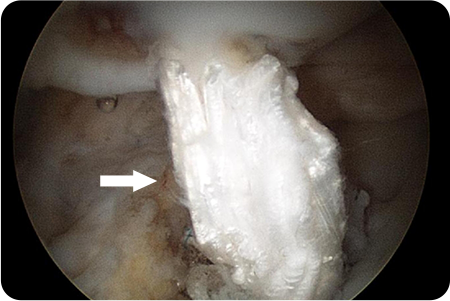

관절경하

석회제거술

어깨 힘줄 조직에 석회질이 침착하여 발생하게 되는

석회성건염이 있을 때 시행하게 됩니다.

관절경을 이용해 석회주변부에서 염증이 생긴

점액낭을 제거함과 동시에 석회 침착물을 제거

합니다.